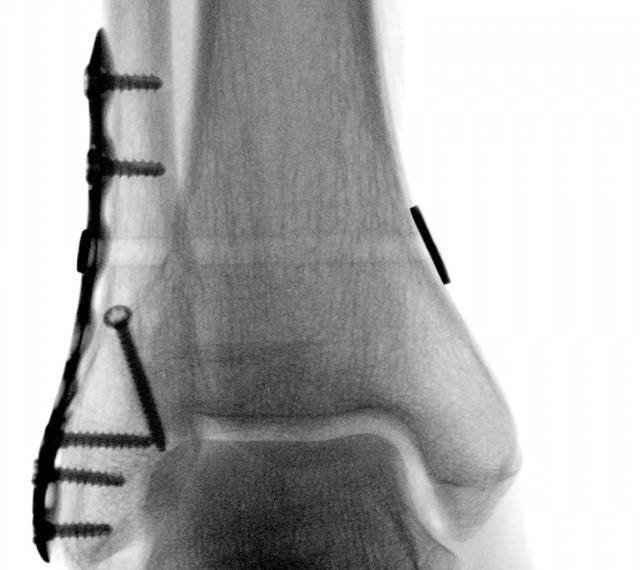

Syndesmosis TightRope® XP Implant System

• Design

• The Syndesmosis TightRope XP implant system features a unique delivery mechanism that allows the user to insert a Syndesmosis TightRope implant without pulling a needle through the medial skin

• Gives the user control to flip the medial oblong button below the skin for less soft-tissue interposition

• Indications

• Provide fixation during the healing process following a syndesmotic trauma

• Fixation of syndesmosis (syndesmosis disruptions) in connection with Weber B and C ankle fracture